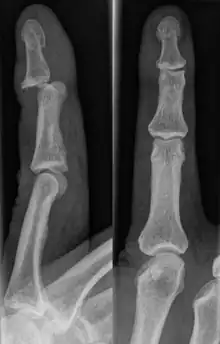

Dislocations can be categorised based on location and type. The finger can be split into three bones and two joints in an alternating order. From the fingertip to the knuckle, these are as follows; distal phalanx, distal inter-phalangeal (DIP) joint, middle phalanx, proximal inter-phalangeal (PIP) joint, and proximal phalanx. DIP dislocations are much less common than PIP dislocations,[2] due to the "stability provided by strong collateral ligaments, palmar plates, and tendinous insertions, as well as the short lever arm of the distal phalanx".[7] Dislocations can be categorised based on the direction that the fingertip moves in relation to the knuckle, be it in the direction of the palm (volar dislocation), or the direction of the back of the hand (dorsal dislocation). Of the two, dorsal dislocations are more common.[3] If reduction has been attempted, an x-ray of the dislocation should appear concentric if successful.[2] However, if there is a fracture present, there will be a misalignment of the joint, which will be evident from the radiograph.[2] Bach suggests a referral to a hand surgeon if a misalignment is present.[2]

Fractures are instances where the bone's structural integrity has been compromised. This is indicated by midshaft pain, as well as visual midshaft angulation or rotation.[3] As with any skeletal injury, an x-ray can be conducted to verify the presence of a fracture.[1] The distal phalanx is especially vulnerable to avulsion fractures, where a fragment of bone is ripped off when the tendon separates from the phalanx.[1] Avulsion fractures are especially common following a first time dislocation.[1] These are especially concerning, as it may indicate a complete tear of the extensor digitorum tendon. If left untreated, this may lead to permanent DIP extensor lag (inability to fully straighten the finger).[8]